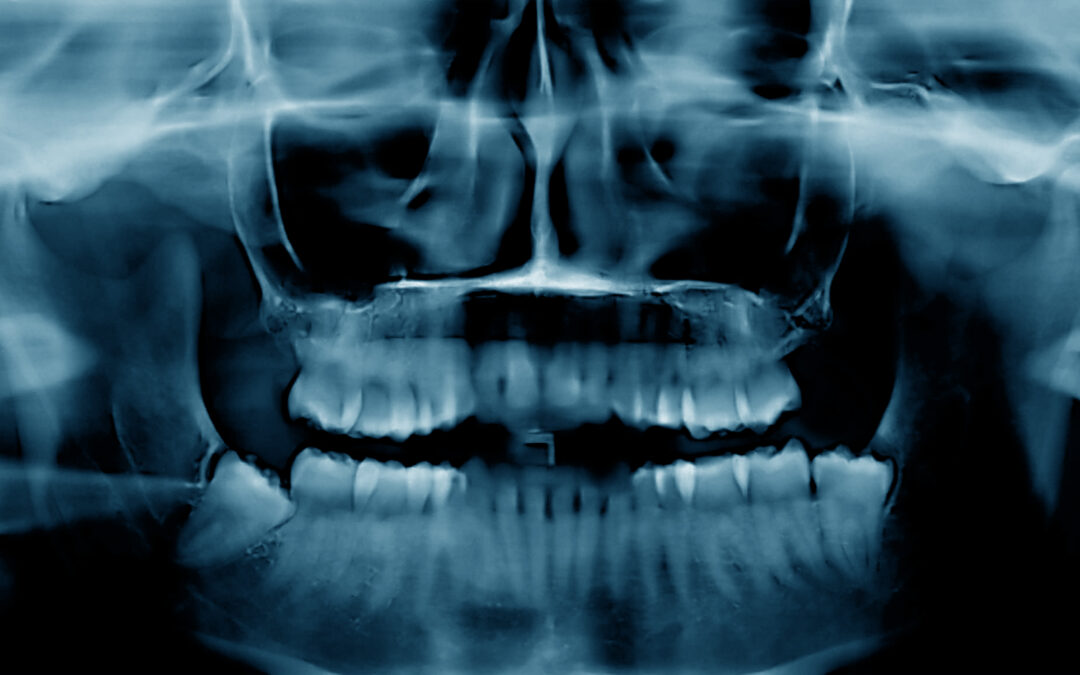

Bone loss in the jaw often happens quietly. Many patients don’t realize it has begun until a tooth becomes loose, their gums recede, or their dentist notes changes on an X-ray. Once bone has disappeared, it’s natural to wonder whether anything can be done to restore it.

Unfortunately, once bone is lost, it does not regenerate on its own. The body cannot naturally rebuild jawbone without intervention. This is why patients missing teeth for many years typically show significant bone loss—and why implants can be more complex in these areas.